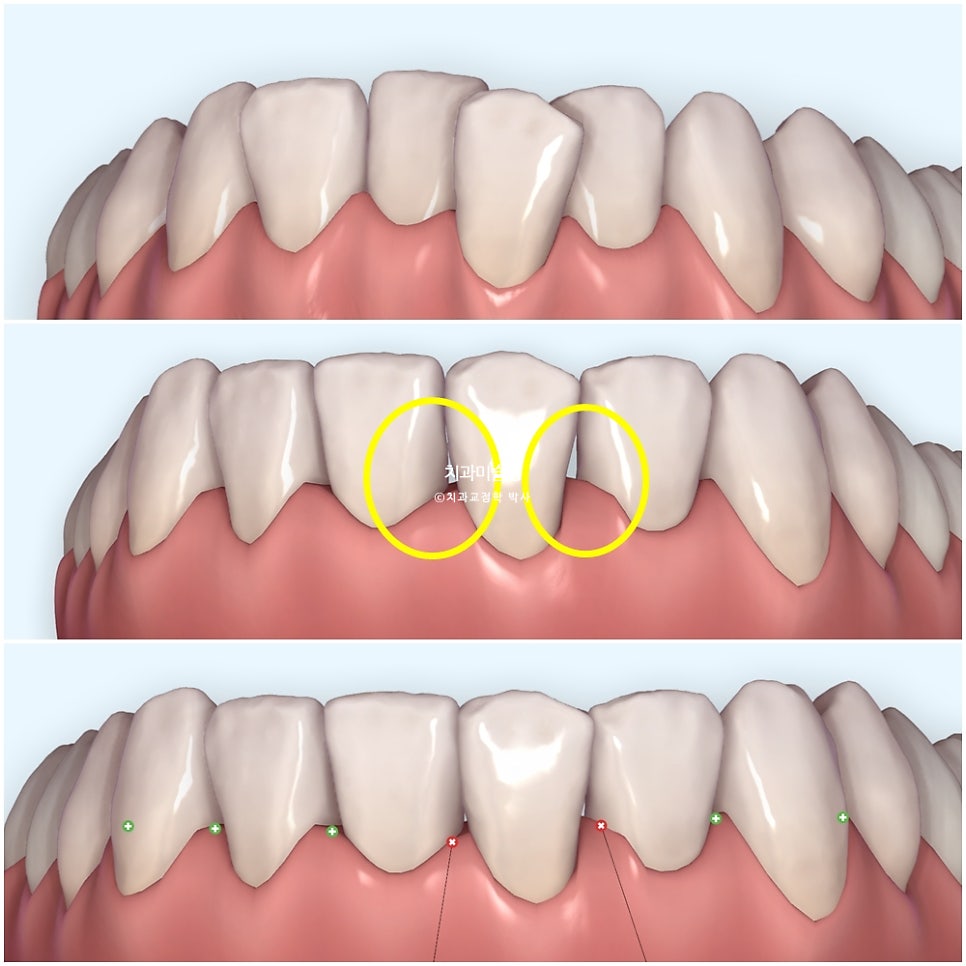

사진은 위에서부터 차례대로

초진

단순 배열 후 블랙트라이앵글의 발생

소량의 치간삭제로 블랙트라이앵글 사이즈가 줄어든 모습 입니다.

치면당 0.2mm를 한계로 설정해놓고 치간삭제를 시행하면 치아가 약해지거나 시릴 가능성은 없습니다.